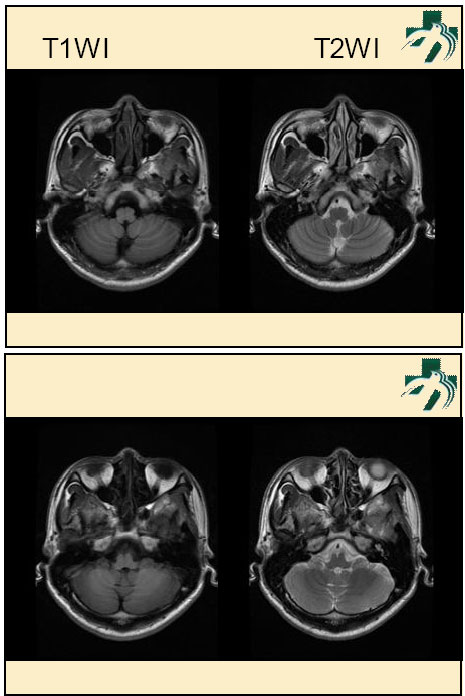

奴卡氏菌感染

第九期三博

读片会

病例之四

北京协和医院 提供

男性,22岁。自觉虫咬后皮疹、肢体麻木4月